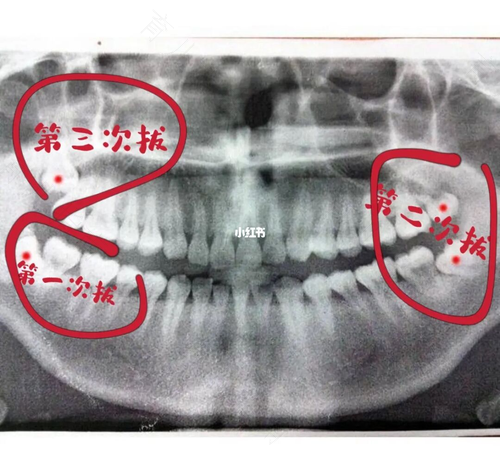

智齿一般位于口腔的后位,由于处处空间狭小,刷牙时很容易忽略,从而导致卫生状况差,引起邻牙龋坏。智牙强行长出,挤压邻牙,会引起邻牙疼痛,造成牙列不齐,因此必须拔掉,那智齿发炎可以拔吗?

智牙由于位置、高度,生长方向的不同,在咀嚼食物时,出现的疼痛感,会带来很大的疼感,长时间会导致下颚关节功能出现异常。牙医建议,在影响口腔健康的情况下,为了避免破坏其他邻牙和组织,智牙必须拔掉。有些正常长出的智牙对咀嚼并没有影响,这样的智牙也可以保留。

智牙所在的位置,在咀嚼过程中会带来疼痛感,会使牙龈肿痛,转变成牙周炎,还会引起骨头病变。智齿发炎有两种,一种是智齿冠周炎,指的是智齿周围牙龈发炎。这时如果拔牙的话,会受到感染,可能还会使病情加重,所以这时不能拔牙,需用药物消除炎症,在去医院进行拔牙。另一种是智牙牙髓发炎,这种情况是可以将智牙拔掉的,因为它不会引起牙龈发炎。